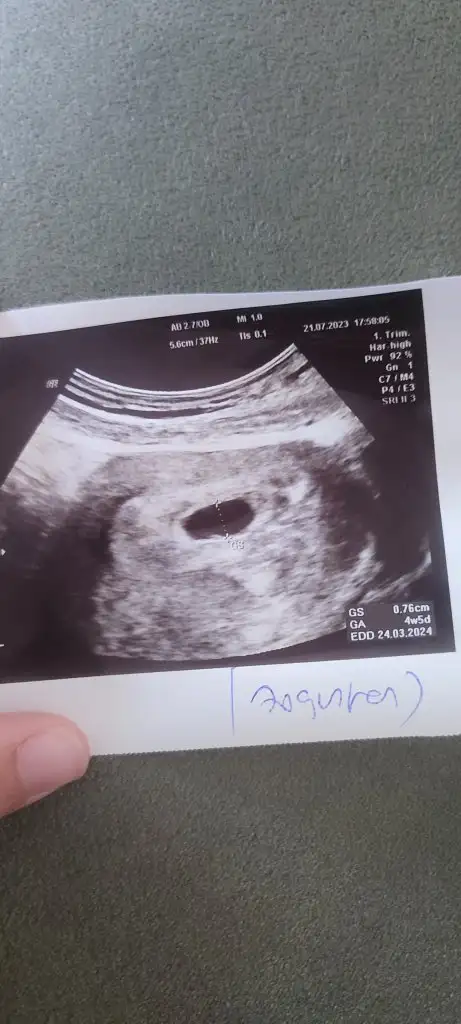

Adetim 8 gün gecikti test yaptım pozitif 2i3 temmuzda beta 141 idi 5 temmuzda 308 çıktı doktor artış iyi 10 gün sonra gelebilirsin dedi gittim kese gördü ama vajinalultarason ile ama bebek gözükmüyor dedi Haftaya yine gel dedi bugün gittim tekrar baktı kese biraz büyümüş hala bebek yok dedi yolk kesesi vs var dedi ve umutlandırmakta istemem dedi, normal şartlarda 8 haftalık olmam gerekirken bu hafta 6 olduğunu söyledi geriden geliyor net tarih veremedi. Beta da bakmak istemedi çünkü kese görüyorum şuan önemi yok dedi böyle. Sizce 15 gün sonra mı gitmeliyim ultrason resmini de ekliyorum. Sizce normal midir baya telaş yaptım çok karışık kafam.